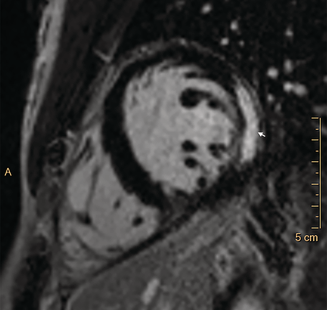

CMR imaging was performed early in most admissions (median, 2 days; IQR, 1–2.5 days); the median interval between peak troponin level and CMR was one day (IQR, 1–2 days). CMR findings were abnormal in 27 of 32 patients (contrast medium could not be administered to one patient because of anxiety), showing late gadolinium enhancement in a patchy subepicardial to transmural pattern, and was especially marked in the inferolateral left ventricular free wall (Box 3). Evidence of oedema in corresponding segments was detected by T2‐weighted CMR in 22 of 32 patients, meeting the Lake Louise criteria for myocarditis.4 The right ventricular apex was affected in isolation in one patient. A small or trace pericardial effusion was noted in 25 of 33 patients, and pericardial enhancement in two of 33 patients. Myocarditis (CDC criteria1) was confirmed for 22 of 32 patients and was probable for ten of 32 patients.